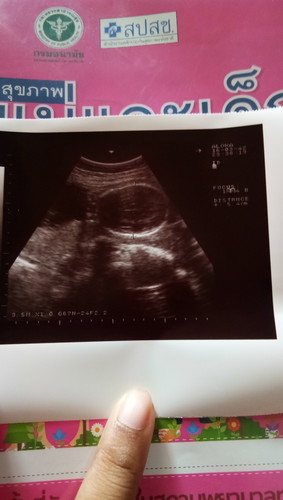

ประจำเดือนมาครั้งล่าสุด10ม.ค.63 ตอนไปฝากท้องครั้งแรกหมอบอก กำหนดคลอด 17 ตุลา63 แต่วันนี้มีอุลต้าซาวหมอบอกว่า มันไม่ตรงกับที่บอกกับคุณหมอ จากที่ได้26วีค ตอนนี้อุลต้าซาวดูได้แค่22วีคเองค่ะ แม่งง มีแม่ๆคนไหนเป็นเหมือนกันไหมค่ะ

บ้านนี้ตรวจครั้งแรกนับจากปจด.แล้วคุณหมอบอก 8 วีค 4 วัน ซาวด์ดูเจอแค่ถุงตั้งครรภ์ไม่เจอน้อง คุณหมอนัดอีก 2 อาทิตย์ซาวด์ใหม่ครั้งนี้เจอน้องวัดขนาดน้องแล้วได้ 1.68 ซม. ตามขนาดอายุครรภ์คือ 8 วีค คุณหมอเลยสรุปได้ว่าไข่แม่ตกช้าอายุที่นับได้จากปจด.กับอายุที่ซาวด์ได้จึงไม่ตรงกันค่ะ

เป็นค่ะหมอนับให้กำหนด5พ.ย.เครื่องอัลตราซาวด์กำหนด15พ.ยคือหมอเค้านับวันที่ประจำเดือนล่าสุดด้วยน่ะค่ะถ้าไข่ตกช้าอายุครรภ์จริงก็จะอ่อนกว่าที่หมอนับค่ะแต่เครื่องอัลตราซาวด์จะวัดจากขนาดมดลูกและตัวเด็กค่ะเลยไม่ตรง